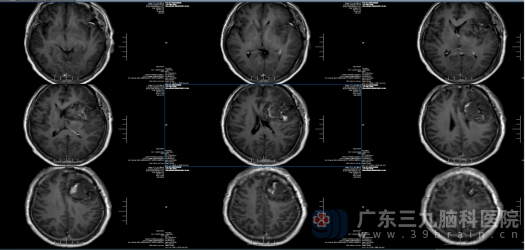

我院神经外十科欧阳辉教授细致阅片后,向家属清晰说明病情:患者左侧额颞岛叶存在大小约54mm×67mm×57mm的肿瘤,左侧额叶部分脑回肿胀,疑似伴脑疝形成,病情危急。结合患者的症状表现与影像学检查结果,科室为卢阿姨完善各项术前相关检查,随后经神经外十科团队集体研讨,明确诊断为左侧额岛叶高级别胶质瘤,制定了精准的手术治疗方案。

影像检查:

术前

术后